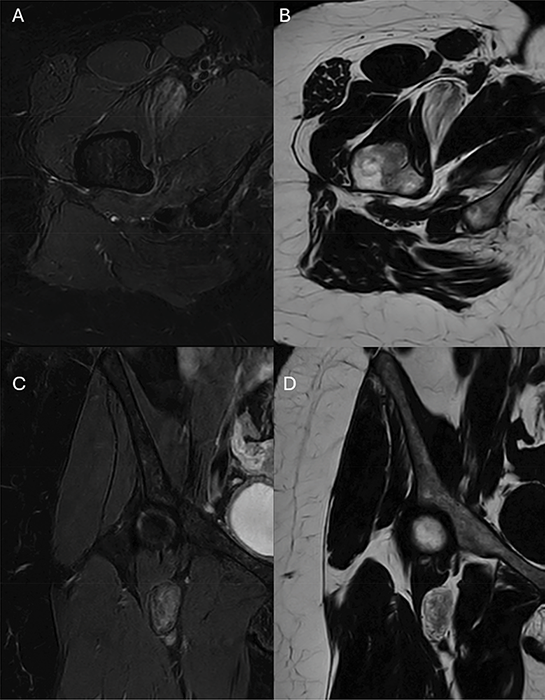

Further evaluation of the lesion was performed using T2 Dixon imaging in the axial and coronal planes. The lesion harbored regions of high signal on the fat‑only images (Figure 2A and C) and with corresponding signal loss on the water‑only images (Figure 2B and D), consistent with macroscopic fat. Interspersed within this fat‑containing lesion were brush‑stroke‑like areas of high signal intensity on the water‑only images and low signal on the fat‑only images, indicating reduced adipose content. However, the absence of complete signal loss suggested that some macroscopic fat remained interspersed within these regions.

Figure 2

T2 Dixon MRI images demostrate the regions of high signal on the fat‑only images (B and D) corresponding to low signal on the water‑only images (A and C) with interspersed brush‑stroke‑like areas of high signal intensity on the water‑only images and low signal on the fat‑only images.